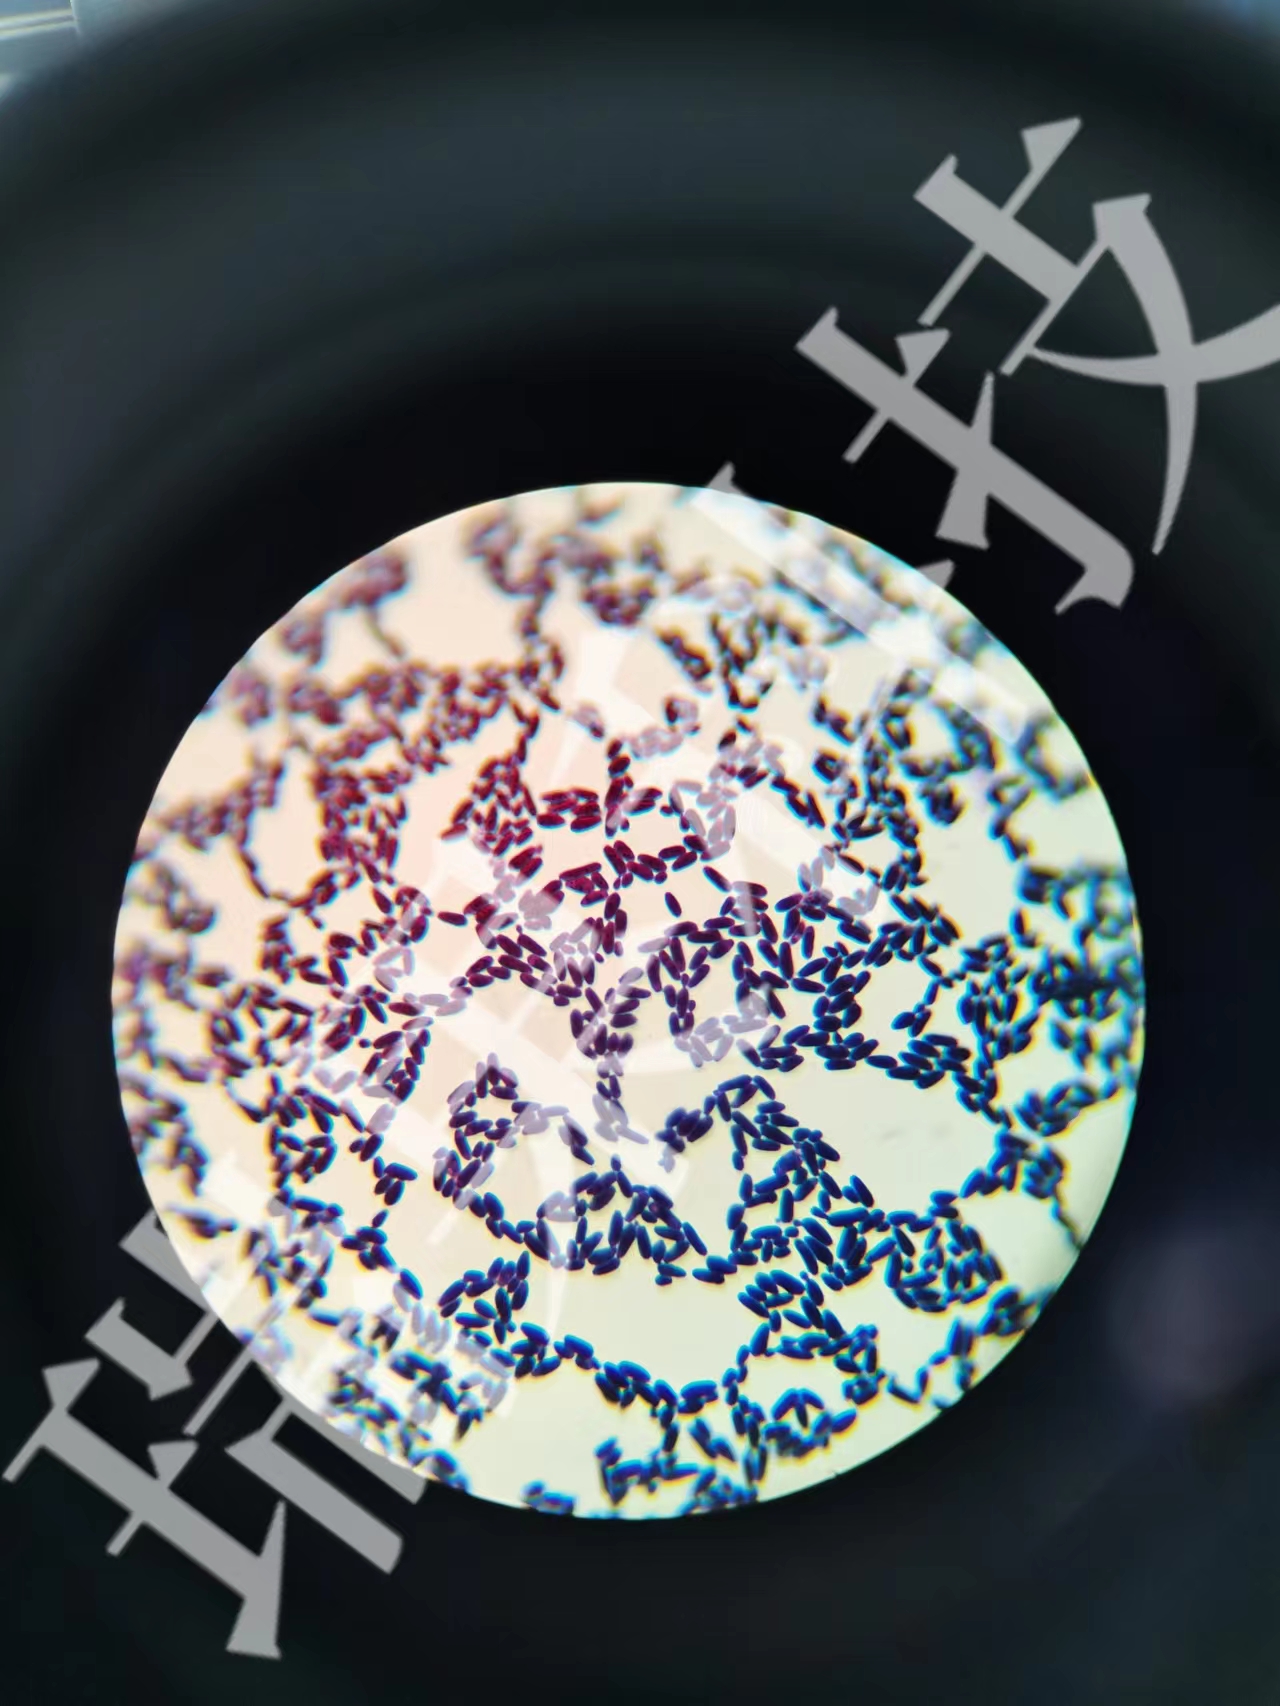

番红o染色:番红(也称作番红O或基本红2)是个用在组织学和细胞学的生物染色剂。番红在一些染色的实验计划表中用作复染剂,将所有的细胞核染成红色。这在革兰氏染色和内孢子染色都是典型的复染剂。它也可以被用

番红o染色:番红(也称作番红O或基本红2)是个用在组织学和细胞学的生物染色剂。番红在一些染色的实验计划表中用作复染剂,将所有的细胞核染成红色。这在革兰氏染色和内孢子染色都是典型的复染剂。它也可以被用来检测软骨、黏蛋白和肥大细胞的颗粒。